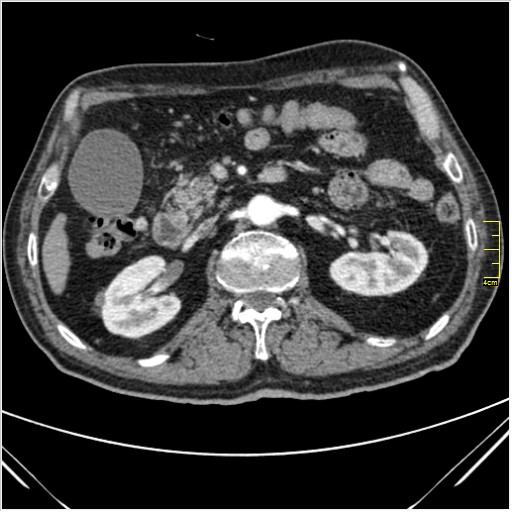

Мужчина 62 года с желтухой

Опухоль головки поджелудочной железы, расширение холедоха и панкреат. протока (Double Channel sign)

Карциномы панкреас гиподенсны на КТ с болюсом, т.к. содержать много соединительной и фиброзной ткани, в отличие от нормальной ткани железы, которая (как любая железа) хорошо васкуляризирована. Поэтому если видим в панкреас солидное гиподенсное образование - всегда настораживает на предмет рака. Второй момент: обязательная оценка взаимоотношения опухоли к ВБА и ВБВ, на предмет оценки операбельности.